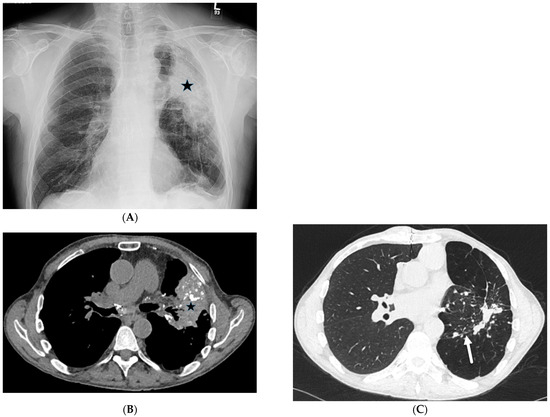

5.2. Kaposi’s Sarcoma

5.3. Lymphoma